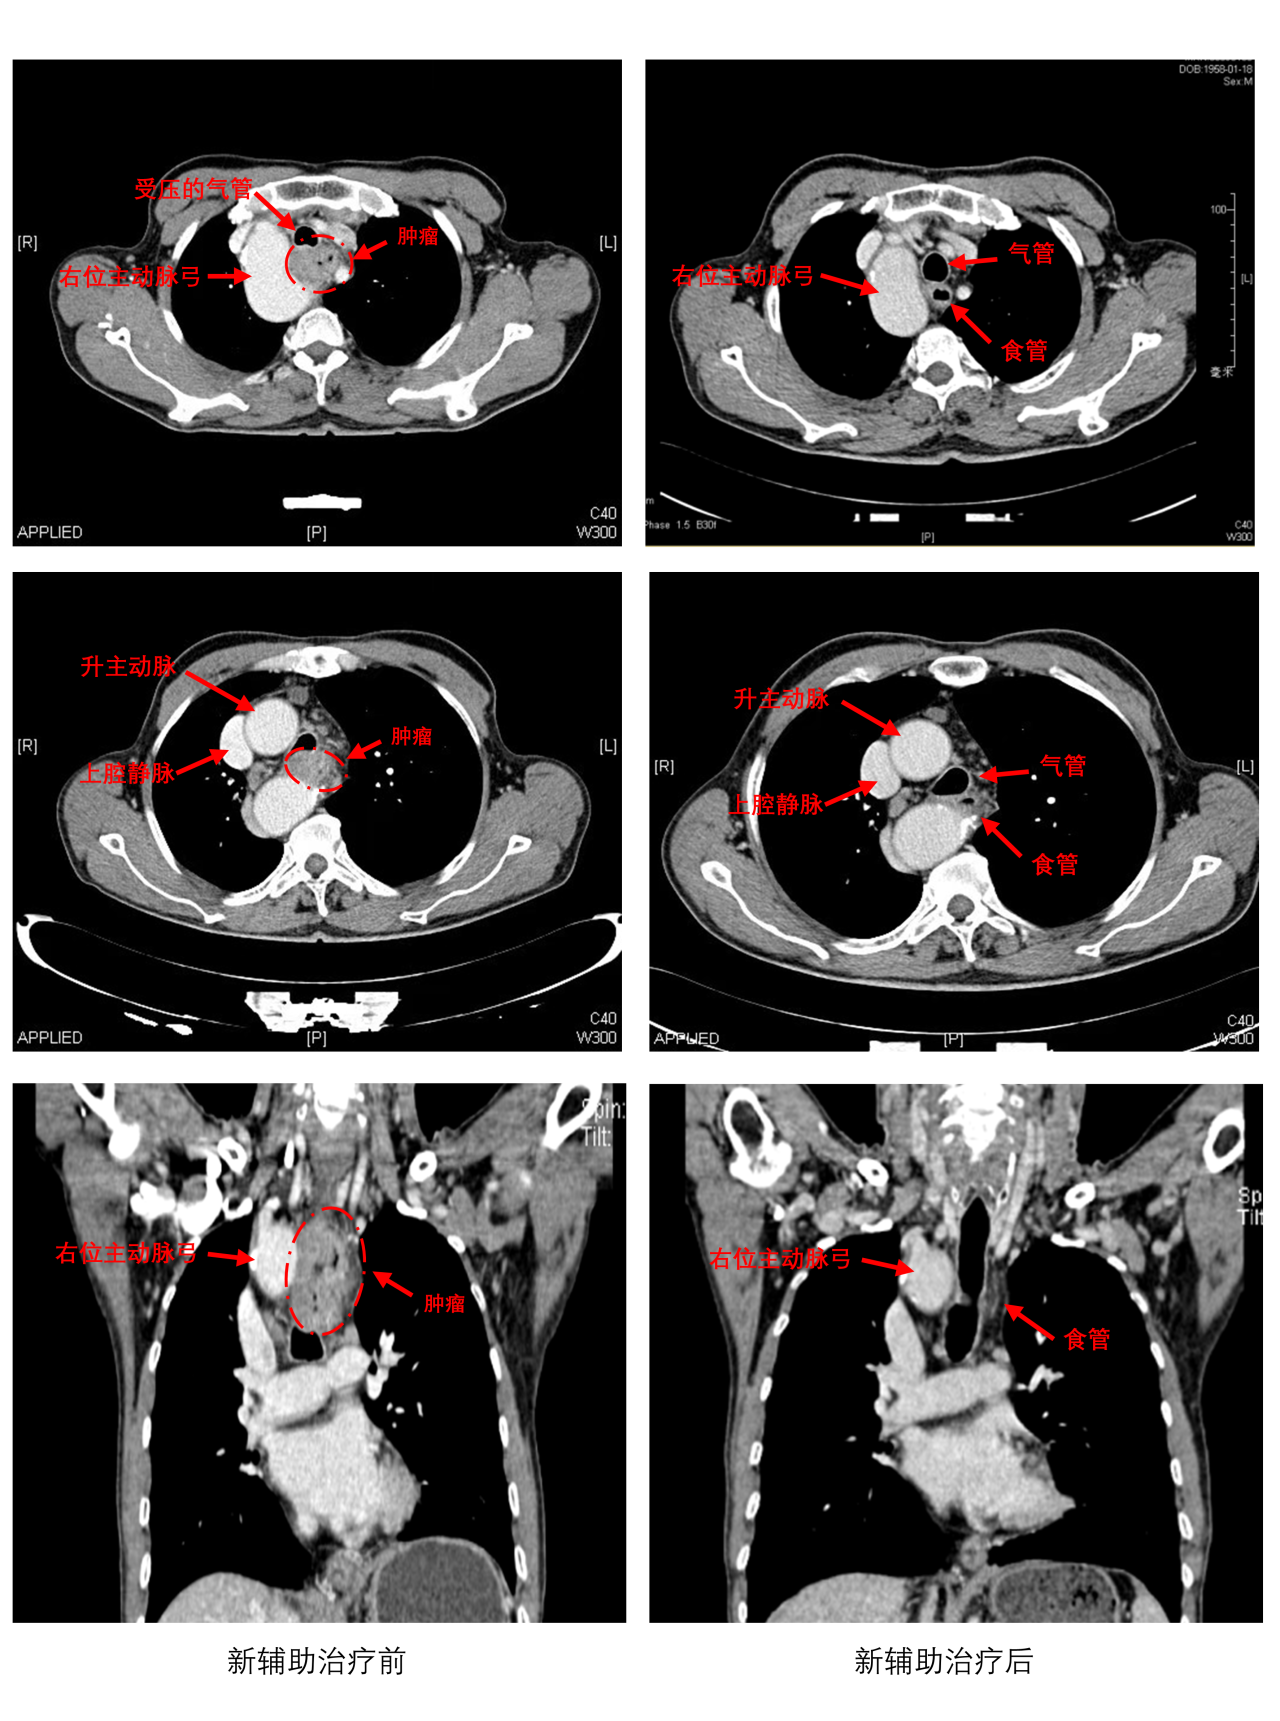

65岁的老乐(化名)身患局部晚期颈段食管癌,同时合并仅0.1%人群存在的右位主动脉弓——犹如在布满血管“迷宫”的咽喉要道拆除“肿瘤炸弹”!

2023年秋,老乐因吞咽困难就医,确诊为颈段食管癌(仅占食管癌5%),且已至局部晚期。更凶险的是,CT检查发现他竟患有右位主动脉弓——一种罕见的先天性血管畸形,导致上纵隔空间极度狭窄,肿瘤紧贴咽喉与异常血管,传统手术极易残留癌细胞或引发大出血。

3周期术前新辅助“化疗+免疫”治疗,肿瘤缩小超过50 %,为手术创造条件;

CT血管成像立体还原血管与肿瘤位置,提前规划手术路径;